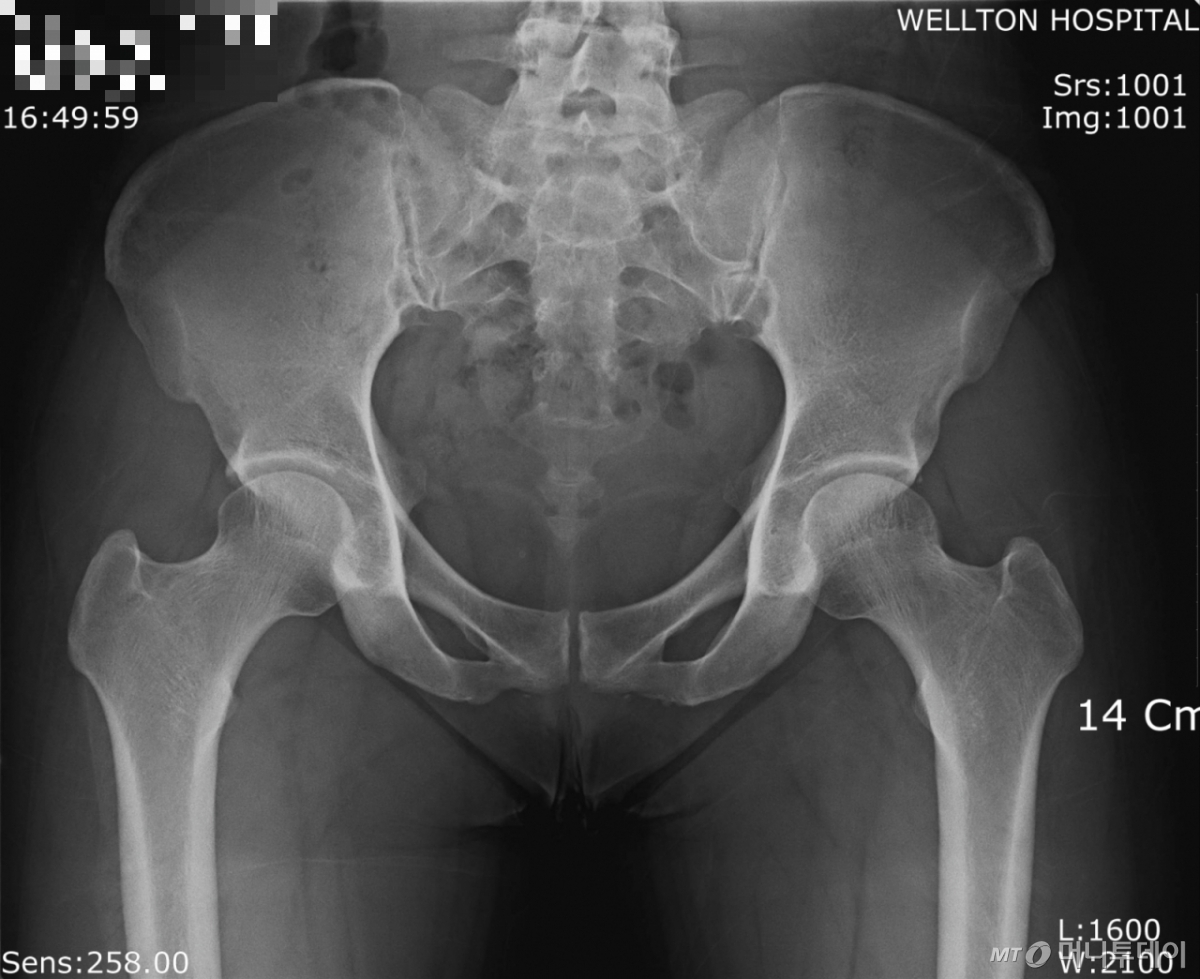

고관절 골절은 골밀도와 근력이 떨어진 어르신이 넘어졌을 때 잘 발생하는 중증 질환이다. 고령자의 고관절 골절은 단순 골절과 달리, 조기 수술과 집중 치료가 예후에 큰 영향을 미친다. 고관절 골절 후 수술받은 환자가 누워지내다가 1년 내 사망할 확률은 14.7%, 2년 내 사망률은 24.3%로 집계됐다. 그렇다고 고관절 골절 후 아예 방치하는 건 더 위험하다. 방치한 사람의 1년 내 사망률이 25%, 2년 내 사망률은 70%에 달해서다.

고관절 골절 수술의 골든타임은 24시간 이내이지만, 늦어도 48시간을 넘기지 말아야 한다. 이보다 수술이 늦어지면 폐렴, 욕창, 심혈관계 합병증 같은 2차 합병증이 발생할 위험이 커진다.